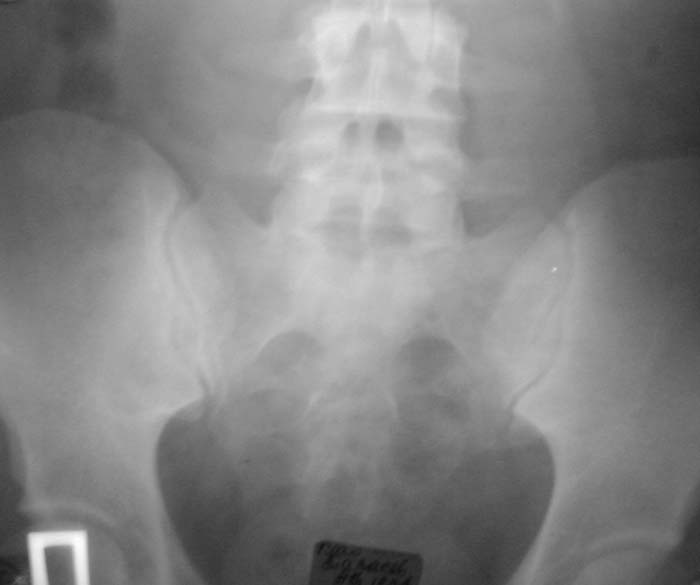

Уважаемые коллеги!Окажите, пожалуйста, консультативную помощь.Мужчина, 24 года. Туберкулез крестцово-подвздошного сочленения справа,

активная фаза. Болен в течение 6 месяцев. Проходил курсы НПВС - без эффекта.Жалобы на постоянные боли в поясничной области. Местно: крестцовая область припухшая, кожа не изменена, при пальпации боль, осевая нагрузка - боль, хромота на правую ногу.Общие анализы - без особенностей.МРТ 09.11.03. - патологических изменений в поясничном отделе не выявлено.Описание рентгенолога: остеосклероз, нечеткость контуров, участки деструкции в правом крестцово-подвздошном сочленении.Положительный анализ на антитела к микобактериям (IgM+E) от 16.10.03.Вопросы: уточнение диагноза, определение тактики лечения.С уважением,А.В.ВладзимирскийДонецкий НИИ травматологии и ортопедииДонецк, Украина

"Представленные рентгенограмы не убедительны с точки зрения наличия деструктивного процесса в крестцово-подвздошном сочленении. Необходимо выполнить компьютерную томографию таза с обязательным захватом крестцово-подвздошных сочленений. Желательно также знать рентгенологическую картину легких."